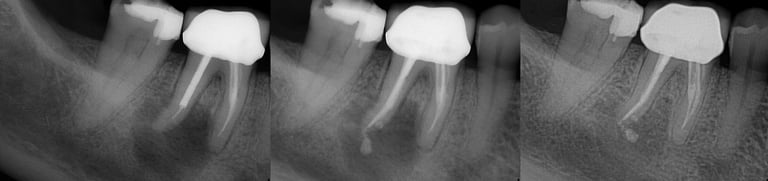

Gallery 1: Initial Cases

Initial Root Canal Cases with preoperative and postoperative radiographs.

#31 RCT